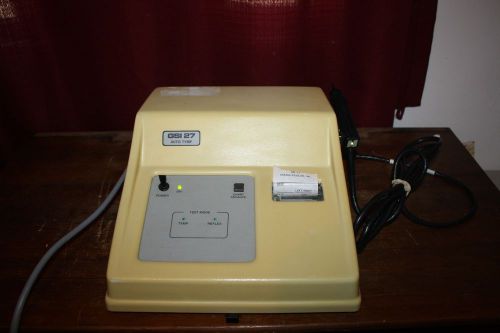

Grason Stadler GSI 27 Auto Tymp 1727